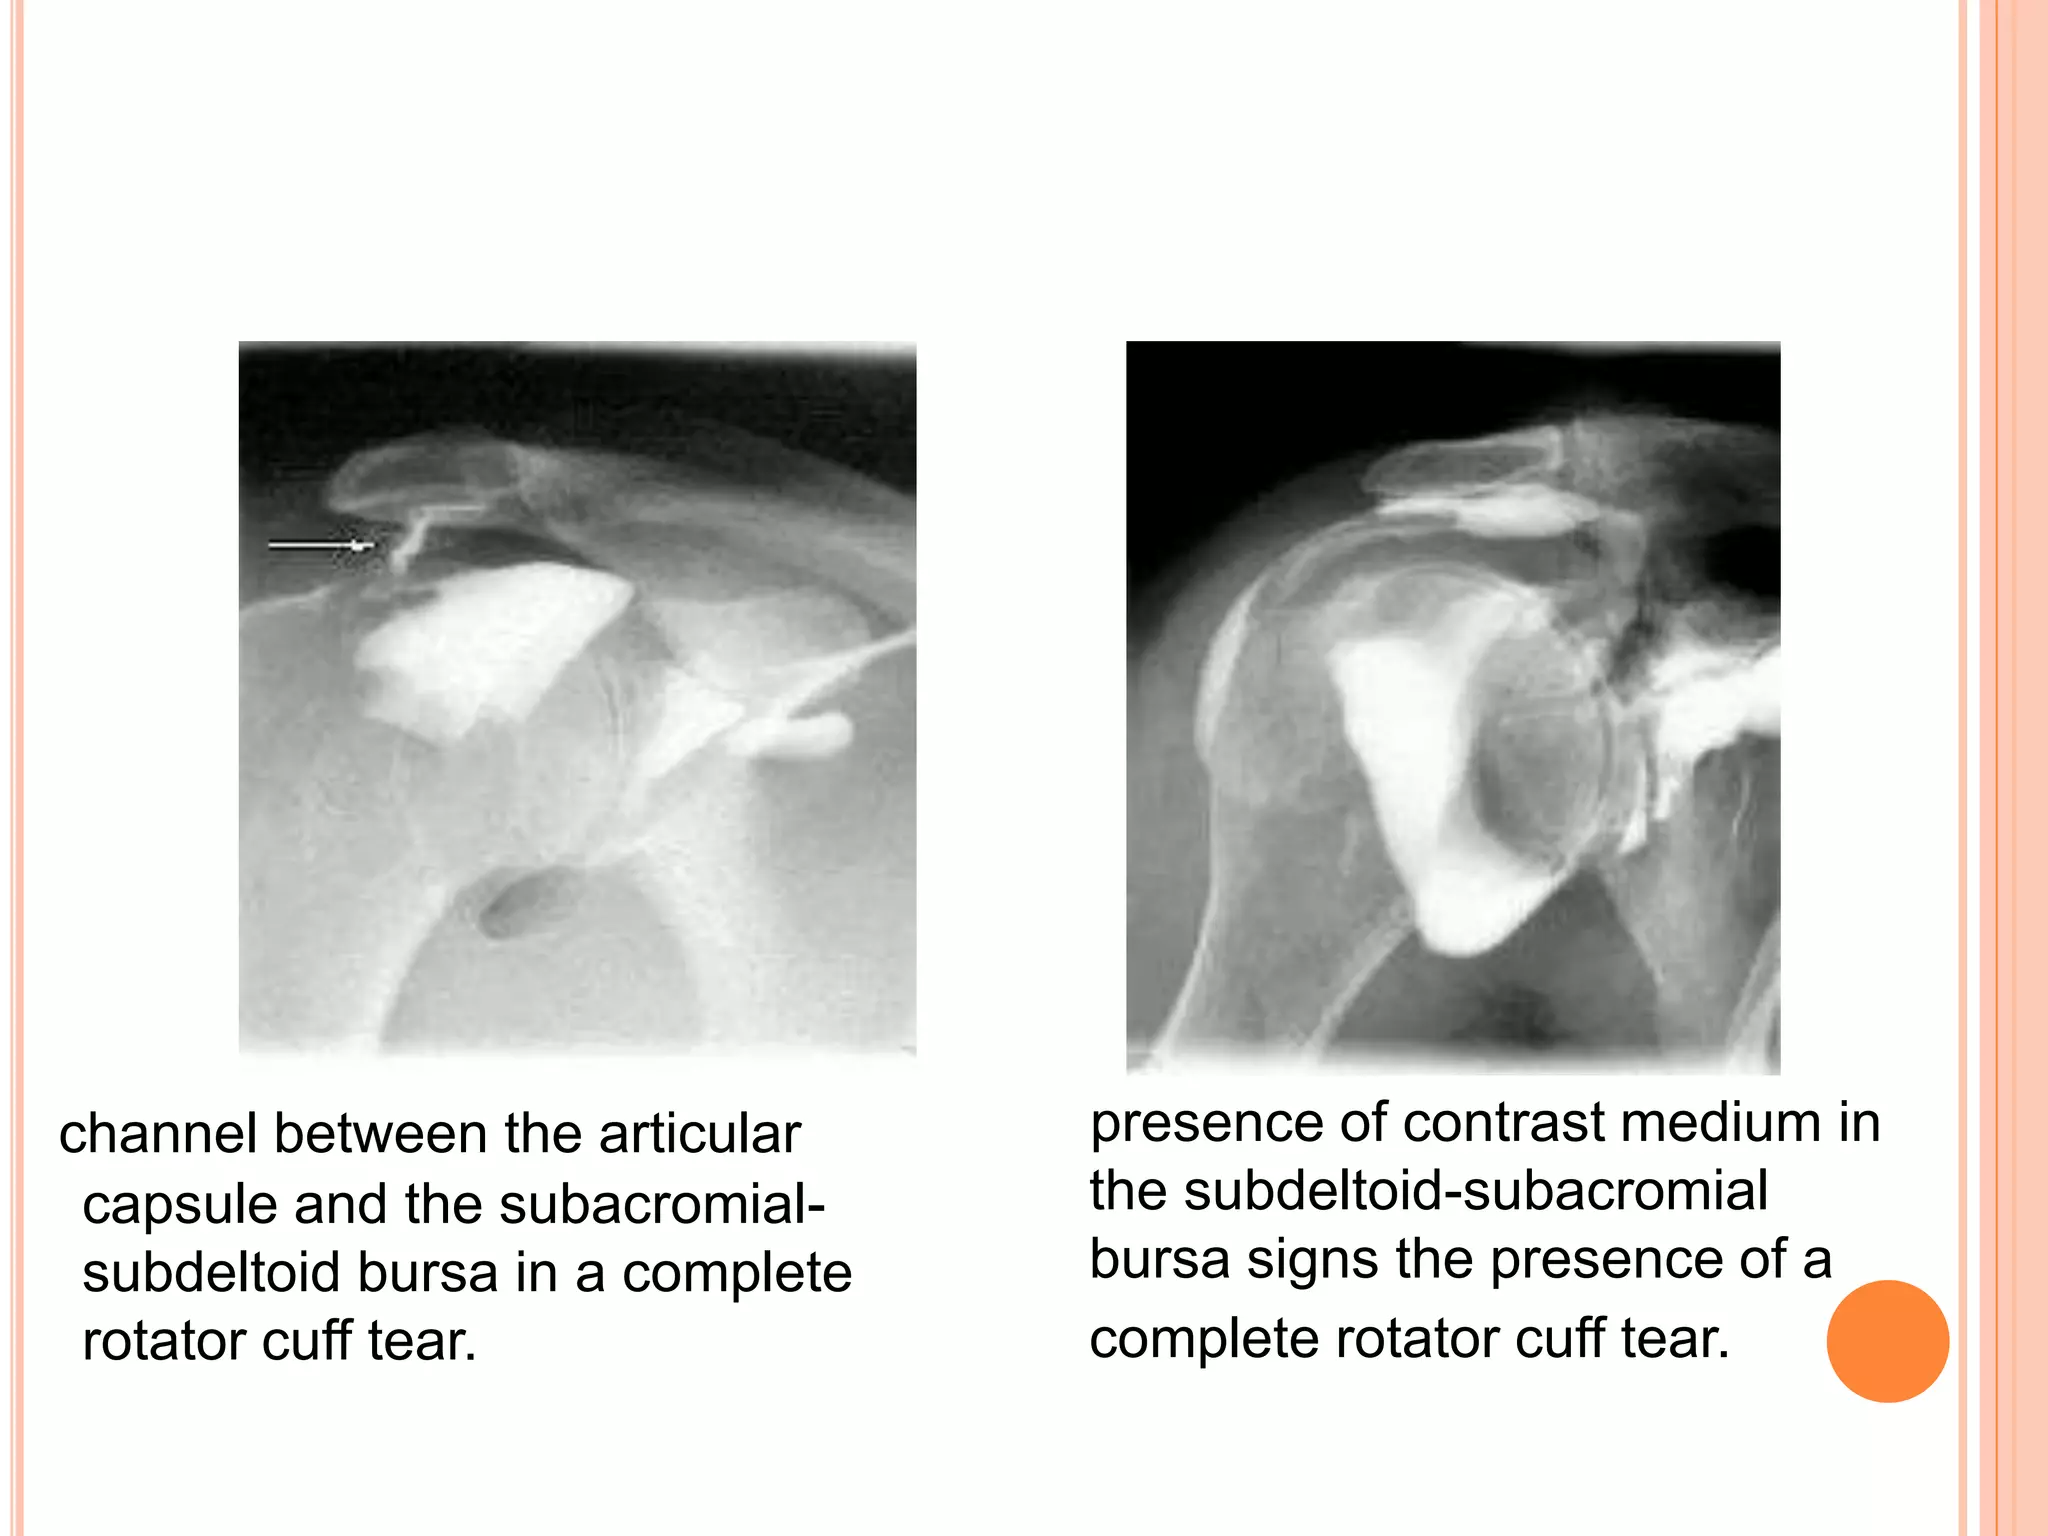

ARTHROGRAM

 Good for diagnosis of complete rotator cuff tear.

 Cost effective.

 Invasive

 Does not give information about size of tear.

presence of contrast medium in

the subdeltoid-subacromial

bursa signs the presence of a

complete rotator cuff tear.

channel between the articular

capsule and the subacromial-

subdeltoid bursa in a complete

rotator cuff tear.

ARTHROGRAM  Good fordiagnosis of complete rotator cuff tear.  Cost effective.  Invasive  Does not give information about size of tear.

presence of contrastmedium in the subdeltoid-subacromial bursa signs the presence of a complete rotator cuff tear. channel between the articular capsule and the subacromial- subdeltoid bursa in a complete rotator cuff tear.